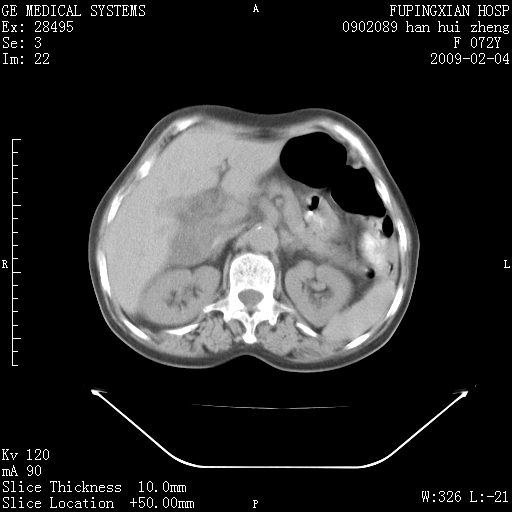

标题: CT17930:F72Y,右腹部包块5日,脐右扪及一包块,触痛。 [打印本页]

标题: CT17930:F72Y,右腹部包块5日,脐右扪及一包块,触痛。

胆囊增大,虽然内壁光滑,但囊壁不均匀性增厚,胆囊窝积液,所以首先考虑胆囊炎,但并不能排除胆囊癌的可能。诊断胆囊癌的依据是:胆囊壁呈不均匀性明显增厚,部分层面胆囊与肝脏界限不清。